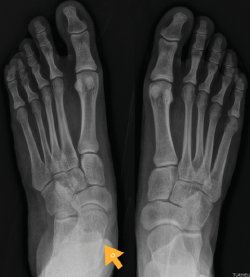

Figura 7. Radiografía del segundo caso: sinostosis talocalcánea media en ambos pies.